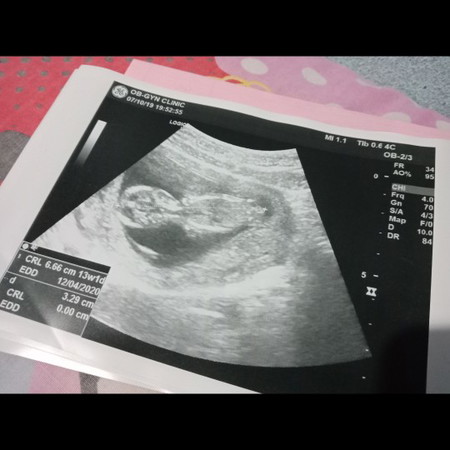

กำลังตั้งครรภ์

ในใบนี้ น้ำหนักของตัวเล็ก บอกมั้ย ดูยังตรงไหนยังไงค่ะ

ในใบนี้ไม่มีค่ะ ลองดูใบอื่นที่เป็นตัวย่อ EFW ค่ะ